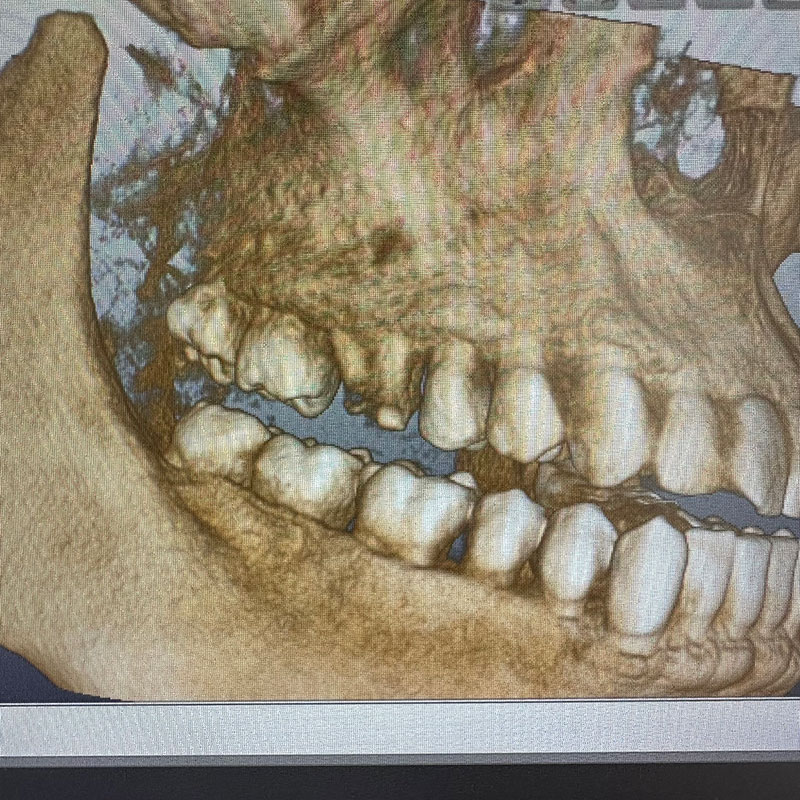

レントゲン写真およびCT画像なのですが、右上6が残歯状態であり歯根破折を起こしている状態でした。しかし歯槽骨から上顎洞底までの距離は十分に認められます。この歯槽骨から上顎洞までの距離がないとソケットリフトなどのオプションの処置が必要になってくるのですが、今回の症例では大掛かりな処置の必要はなく症例の難易度としては比較的イージーな方でした。上顎洞などに関して知りたい方はこちらのページを参照にしていただければと思います。